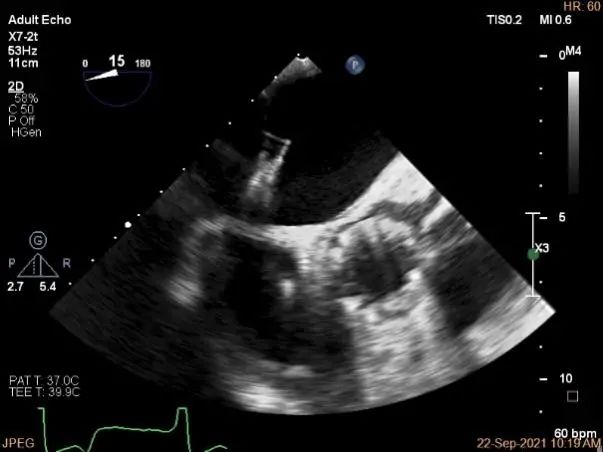

术前超声评估

术中超声

房间隔穿刺点选择

穿刺高度:4.3cm